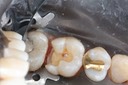

Scott Kanamori #31 pre-op

Scott Kanamori #31 amalgam removal

Scott Kanamori #31 prep